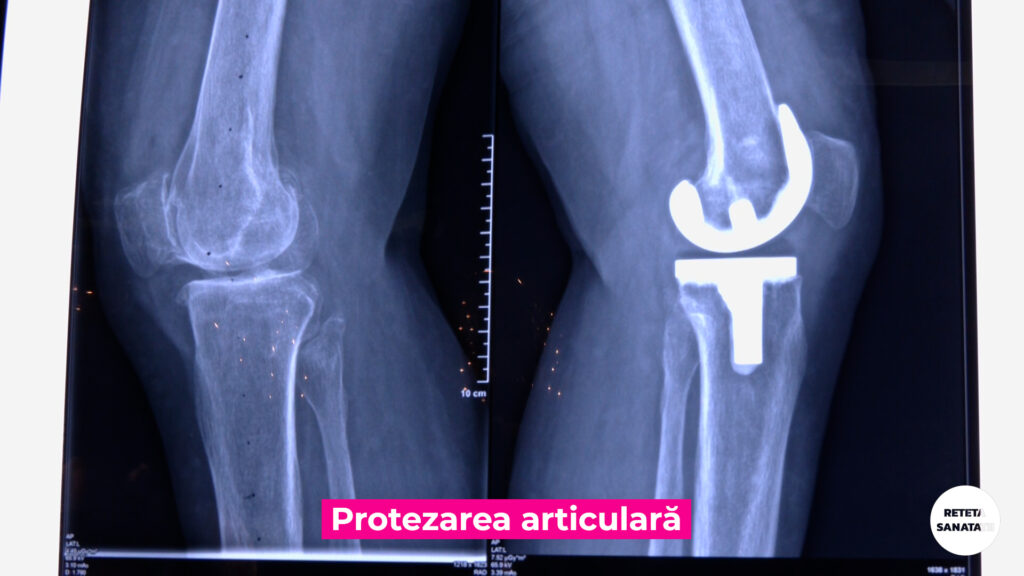

Artroplastia reprezintă o procedură chirurgicală utilizată pentru a reface integritatea și funcția unei articulații.

Distrugerea ireversibila a articulatiilor poate fi cauzata de artroze- afectiuni cronice degenerative ale cartilajului si elementelor osoase – precum si de traumatisme.